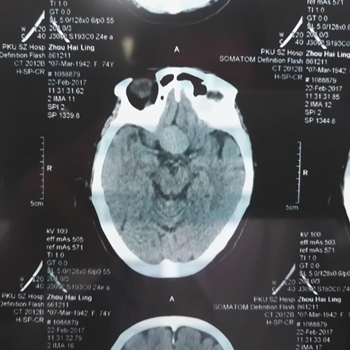

于是邢主任给她做了进一步检查,通过OCT与视野计检查结果,邢宝刚主任判断张奶奶视野缺损的情况应该不是单纯的眼睛问题,极有可能是脑内肿瘤引起的。于是邢宝刚主任建议张奶奶去做脑部CT扫描检查。

没想到,这一查,果然脑部长了一个约21*25mm大小的肿瘤,就是它压迫了视神经,导致视野缺损。“脑子里的肿瘤,这个尺寸已经是很大的了。”